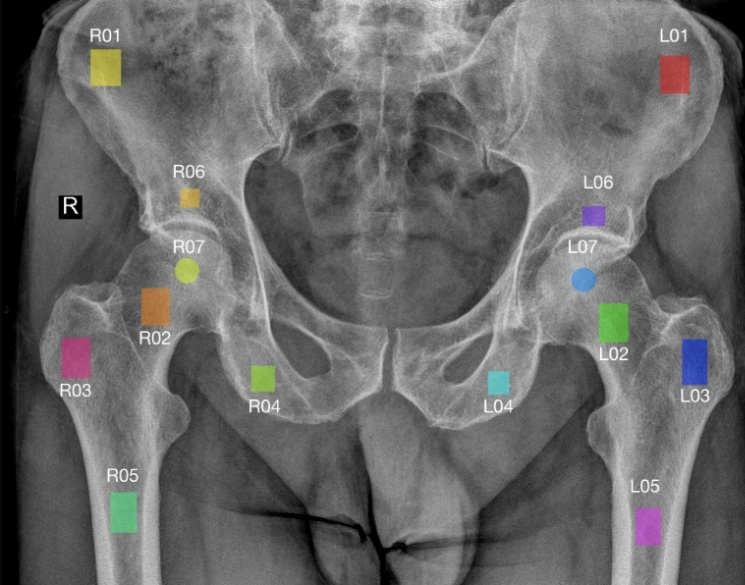

Czy analiza obrazu rentgenowskiego sąsiednich kości może pomóc w wykrywaniu artrozy stawu biodrowego (ASB)? 🤔

Badania pokazują, że nawet fragmenty kości miednicy i udowych zawierają istotne informacje o stanie stawu biodrowego - a zastosowanie odpowiedniego przetwarzania obrazu (m.in. CLAHE, normalizacja Z-score) znacząco poprawia skuteczność detekcji.